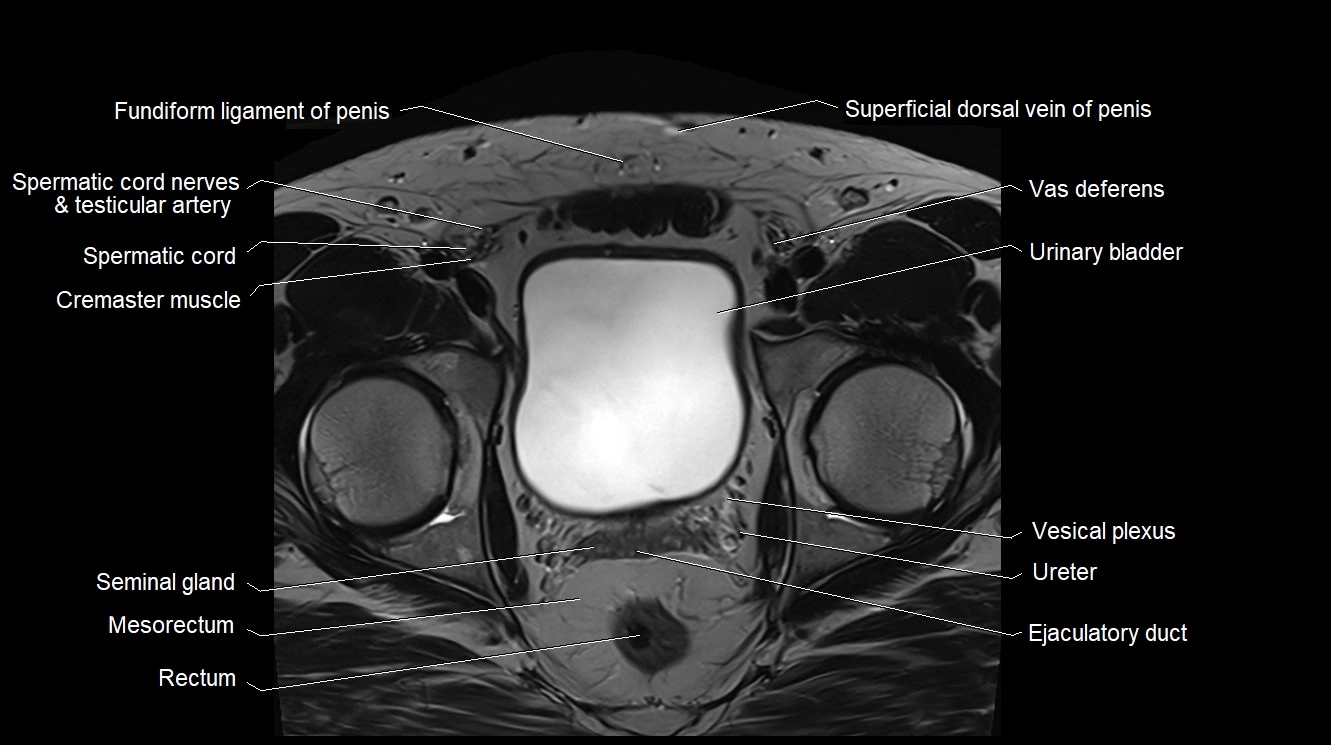

- Cremaster muscle

- Ejaculatory duct

- Fundus of urinary bladder

- Median umbilical ligament

- Mesorectum

- Rectum

- Seminal vesicle

- Spermatic cord

- Spermatic cord nerves

- Superficial dorsal vein of penis

- Urinary bladder

- Vas deferens

- Vesical venous plexus